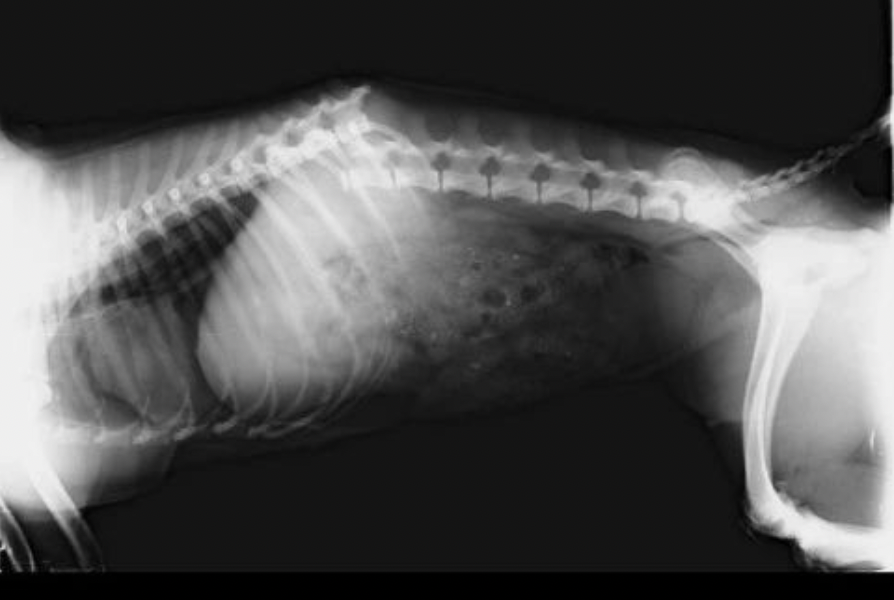

Ada juga anak kaki empat yang disiksa hingga alami patah tulang di punggungnya. Dokter pun sampai menyerah saat itu, suara “kaing kaing” melengking kesakitan buat Miracle tak bisa apa-apa. Hanya tengkurap pasrah.

Ucap dokter, kalaupun harus operasi dan berobat, kecil kemungkinan untuk berhasil. Cerita Ci Fang-Fang..

“Keajaiban Tuhan menyertai anak kaki empat ini Ka, makannya saya kasih nama Miracle. Operasi besar sedemikian rupa dengan kesempatan hidup yang kecil berhasil dilaluinya..”